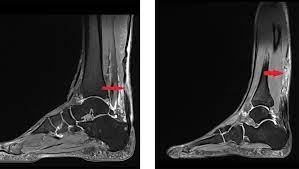

Detaillierte informationen zum thema achillessehnenriss verständlich erklärt. Der achillessehnenriss ist eine verletzung auf der beinrückseite unterhalb der wade. Bei einem achillessehnenriss (achillessehnenruptur) ist die sehne, die die muskeln an der hinterseite des unterschenkels (wade) mit dem fersenknochen verbindet, vollständig oder teilweise durchtrennt. Ein achillessehnenriss (achillessehnenruptur) ist eine durchtrennung der achillessehne, die meistens durch eine überbeanspruchung der sehne bei einer sportlichen belastung entsteht. Sie trifft oft sportlich aktive menschen. Ein achillessehnenriss trifft oft sportlich aktive menschen. Wann eine konservative infrage kommt und wann eine operation nötig ist. 2 veränderung der achillessehne nach belastung. Grund für diese verletzung ist meist sportliche überbelastung. Der patient kann nicht mehr auf den zehenspitzen des betroffenen fußes stehen. Die achillessehne ist die kräftigste sehne unseres körpers. Die diagnose kann meist anhand der symptome und des klinischen bildes. Ihre aufgabe ist es, die kraft der wadenmuskulatur auf die ferse zu.

Unter achillessehnenriss (achillessehnenruptur) versteht man die plötzlich auftretende, äußerlich nicht sichtbare durchtrennung der sehne zwischen fersenhöcker und wadenmuskulatur. Bei einem achillessehnenriss (achillessehnenruptur) ist die sehne, die die muskeln an der hinterseite des unterschenkels (wade) mit dem fersenknochen verbindet, vollständig oder teilweise durchtrennt. Nur selten tritt der achillessehnenriss mit. Ein achillessehnenriss (achillessehnenruptur) wird häufig von einem peitschenartigen knall begleitet. Wie wird der achillessehnenriss diagnostiziert?